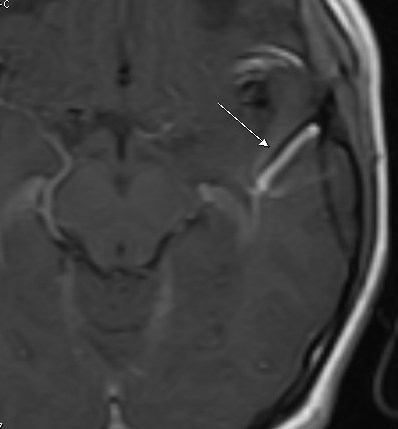

Angiomas or developmental venous anomalies (DVA) refer to a set of benign tumors derived from cells of the endothelium or the tissues surrounding these vessels. These tumors may be an indication of systemic problems such as liver disease. However, angiomas are usually not associated with malignancy. They represent the concept of functional and anomalous venous channels present in the brain parenchyma. Venous angioma is a kind of congenital variant of cerebral venous drainage. On imaging, angiomas are visible as several small-sized deep parenchymal veins that converge toward collecting veins. Venous angioma or DVA are usually not interrelated with any other vascular malformations harboring hemorrhage risks. However, separated or isolated DVA usually appears as benign lesions with a link demonstrable to seizures, headaches, or hemorrhage.

These angiomas most commonly occur either in the Frontoparietal morphea or cerebellar hemisphere. They exhibit a caput medusae sign of veins draining into a relatively large vein.

Developmental venous anomalies or venous angiomas are asymptomatic and, for this reason, it is not easy to diagnose them. Angiomas can only be diagnosed when an individual has imaging tests to look into the cause of several other problems. The imaging tests may include MRI or MRA, conventional angiogram. These tests also include specific CT scans that show areas affected by the blood flow. The majority of the people are unaware that they have a DVA condition and it is only diagnosed after their death if an autopsy gets done.